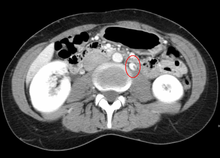

The nutcracker syndrome (NCS) — is a manifest variant of nutcracker phenomenon, renal vein entrapment syndrome, or mesoaortic compression of the left renal vein. It results most commonly from the compression of the left renal vein between the abdominal aorta (AA) and superior mesenteric artery (SMA), although other variants exist.[1][2] The name derives from the fact that, in the sagittal plane and/or transverse plane, the SMA and AA (with some imagination) appear to be a nutcracker crushing a nut (the renal vein). There is a wide spectrum of clinical presentations and diagnostic criteria are not well defined, which frequently results in delayed or incorrect diagnosis.[1] This condition is not to be confused with superior mesenteric artery syndrome, which is the compression of the third portion of the duodenum by the SMA and the AA.